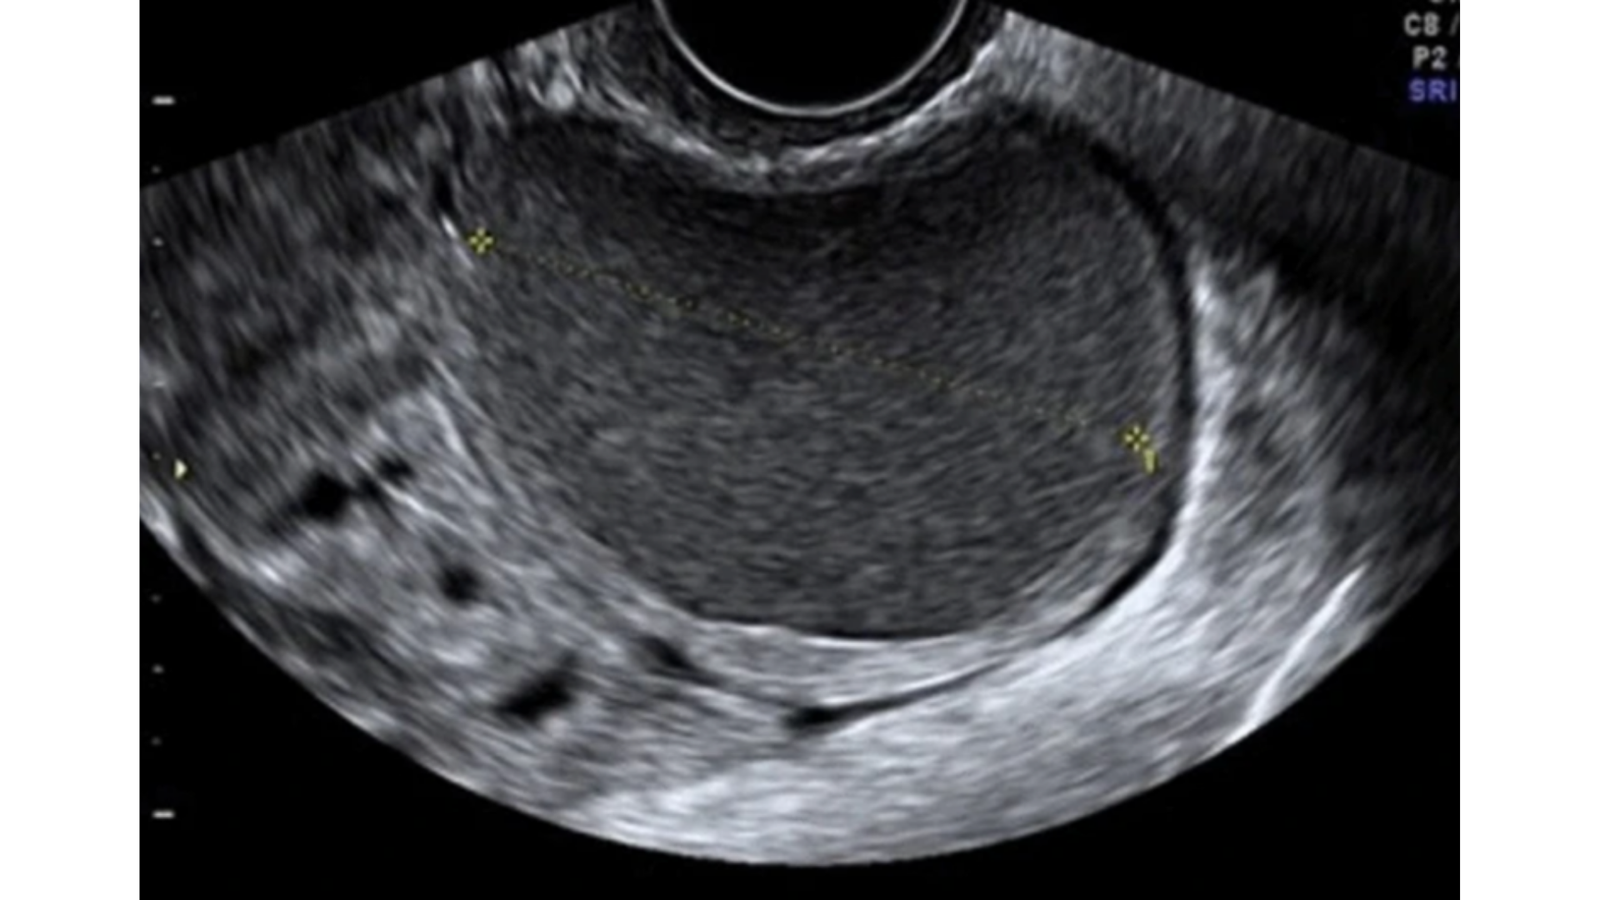

Quiste endometriósico, con parénquima regular en la periferia, denominado “signo de la media luna”, característico de las lesiones benignas. Ausencia de vascularización intralesional (fig2).